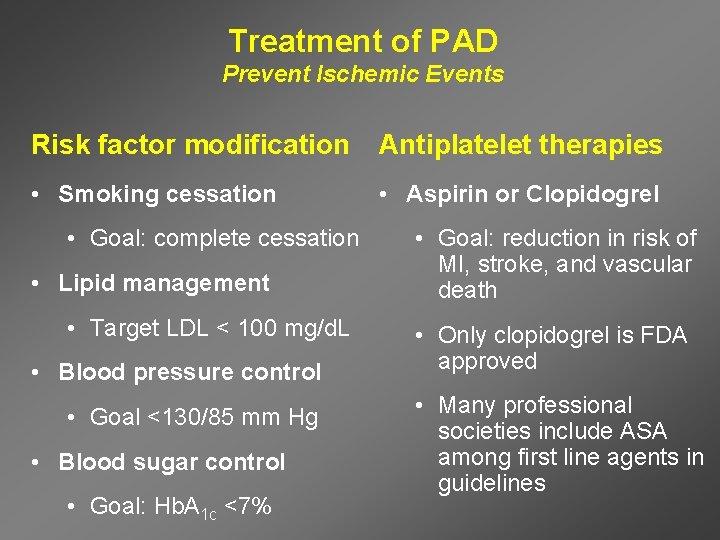

Treatment of PAD Prevent Ischemic Events Risk factor modification Antiplatelet therapies • Smoking cessation • Aspirin or Clopidogrel • Goal: complete cessation • Lipid management • Target LDL < 100 mg/d. L • Blood pressure control • Goal <130/85 mm Hg • Blood sugar control • Goal: Hb. A 1 c <7% • Goal: reduction in risk of MI, stroke, and vascular death • Only clopidogrel is FDA approved • Many professional societies include ASA among first line agents in guidelines